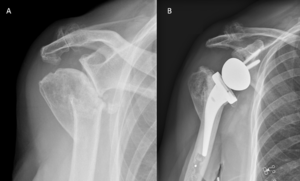

Revision Arthroplasty

Revision surgery after primary shoulder arthroplasty (i.e. hemiarthroplasty, resurfacing or total shoulder arthroplasty) produced high patient satisfaction (Figure). It is, however, associated with higher complication and failure rates compared to reverse shoulder arthroplasty for patients without previous arthroplasty.[93]

A) Anteroposterior radiograph of a failed anatomic total shoulder arthroplasty; B) Anteroposterior post-operative radiograph after reverse shoulder arthroplasty.